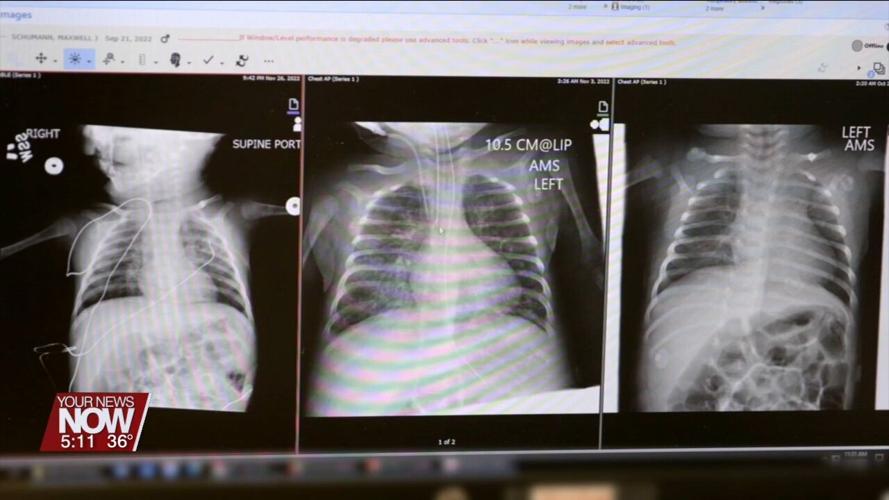

And that was the case for Max. He was intubated for ten days before showing signs of improvement.